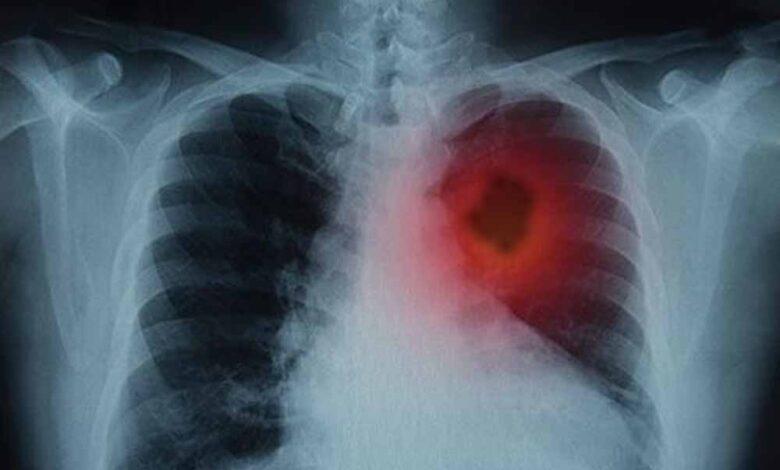

फेफड़ों के कैंसर से जूझ रहे लाखों लोगों के लिए विज्ञान की दुनिया से एक बहुत बड़ी और राहत भरी खबर आई है। दरअसल, वैज्ञानिकों ने एक ऐसा तरीका खोजा है जिससे फेफड़ों के ट्यूमर को उसकी सबसे बड़ी कमजोरी पर वार करके खत्म किया जा सकता है। जी हां, इस शोध के दौरान, उन्होंने एक बेहद जरूरी प्रोटीन की पहचान की। बता दें, यह प्रोटीन कैंसर कोशिकाओं को ‘मरने’ से बचाता है। ऐसे में, शोधकर्ताओं का कहना है कि अगर इस खास प्रोटीन की गतिविधि को रोक दिया जाए, तो कैंसर कोशिकाएं खुद-ब-खुद नष्ट होने लगती हैं और ट्यूमर सिकुड़ जाता है।

हाल ही में शोधकर्ताओं ने फेफड़ों के कैंसर की एक महत्वपूर्ण कमजोरी का पता लगाया है- एक ऐसा प्रोटीन, जिसे रोक दिया जाए तो कैंसर कोशिकाएं खुद को ही नष्ट करने लगती हैं। यह खोज न सिर्फ इलाज के नए रास्ते खोलती है, बल्कि भविष्य में ऐसे कई मरीजों के लिए जीवनदायिनी साबित हो सकती है, जिन्हें अब तक सीमित विकल्प ही उपलब्ध थे।